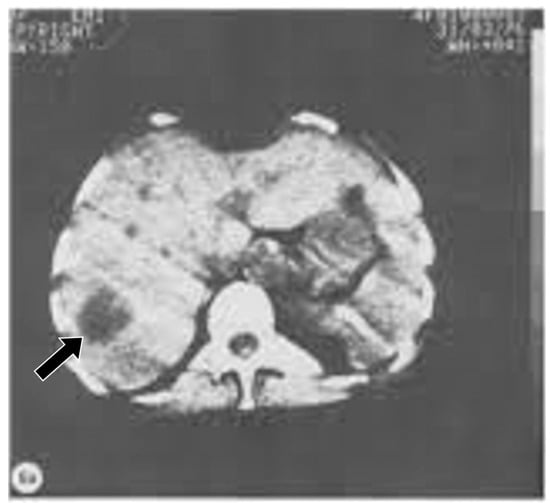

The first major revolution in soft tissue contrast in medical imaging came in 1971 with the introduction of brain computed tomography (CT) [5,6]. The technique not only produced slices of the brain that were much more useful than conventional tomography, but it directly displayed brain tissue. Within the brain, there was high intrinsic contrast between normal and abnormal tissues so that lesions such as the glioma shown in Figure 5 could readily be seen because its signal was lower than that of normal brain. The intrinsic contrast was present without requiring the use of a contrast agent (such as air and iodinated compounds). When intravenous iodinated contrast agents were used with CT, additional information was obtained. CT transformed the practice of neuroradiology from 1971 onwards, and body imaging from 1975 onwards as well (Figure 6).

Figure 5.

First patient examined with CT, frontal cystic glioma (October 1971) [5]. CT produced images of slices of the brain, which was a major improvement over conventional tomography. Signal is seen from the brain in this 80 × 80 matrix image. In addition, there is negative intrinsic contrast between the cystic glioma (black arrow) which is lower signal (darker) than the surrounding normal brain.